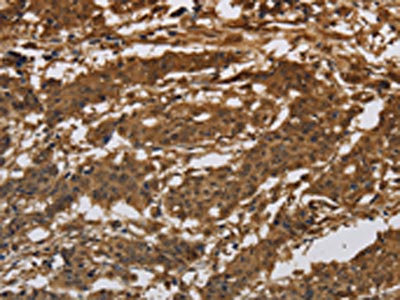

• The image on the left is immunohistochemistry of paraffin-embedded Human gastic cancer tissue using CSB-PA939542(ITGB7 Antibody) at dilution 1/30, on the right is treated with synthetic peptide. (Original magnification: ×200)

• The image on the left is immunohistochemistry of paraffin-embedded Human liver cancer tissue using CSB-PA939542(ITGB7 Antibody) at dilution 1/30, on the right is treated with synthetic peptide. (Original magnification: ×200)